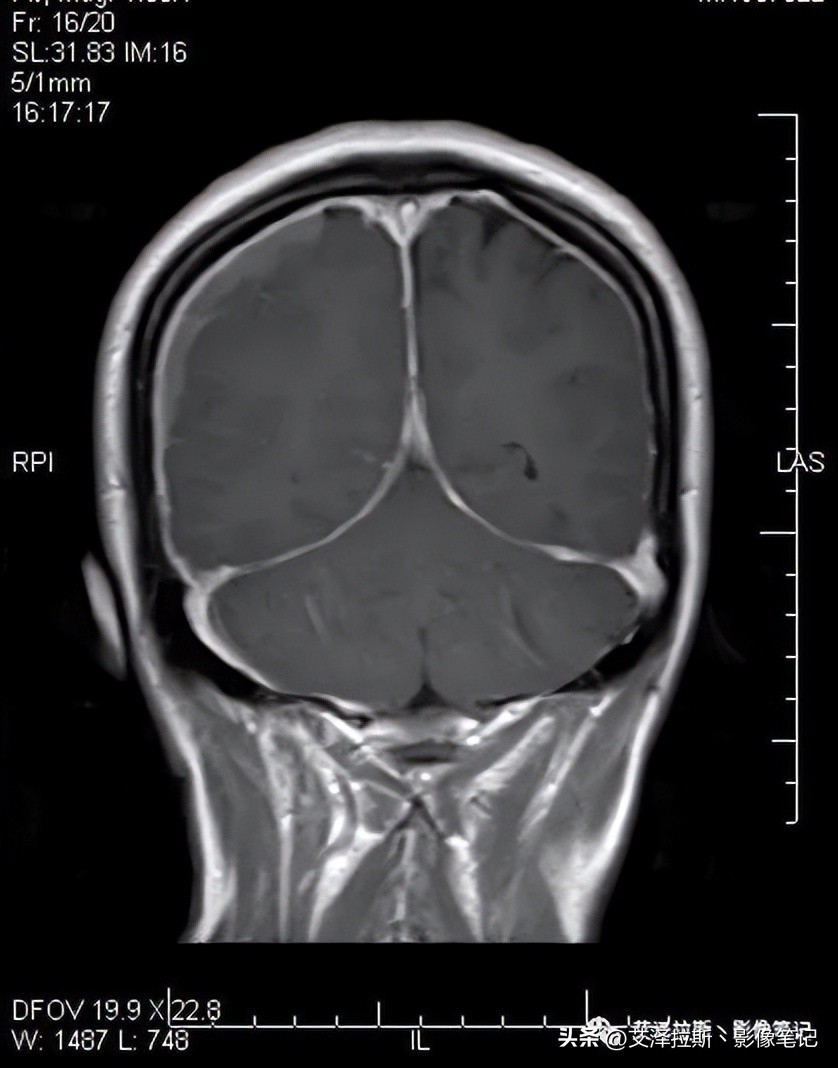

图1 T2WI

图1-4显示右侧硬膜下血肿(亚急性-慢性期)、大脑镰硬膜下血肿(亚急性期),小脑幕硬膜下血肿(未提供图片);图7-9显示硬脑膜增厚,明显均一强化,未见结节状强化,柔脑膜未见强化。

- 低颅压综合征;

- 右侧硬膜下血肿(亚急性-慢性期)、大脑镰硬膜下血肿、小脑幕硬膜下血肿(亚急性期)。

低颅压综合征在影像上主要表现为四联征:

1.弥漫性硬脑膜增厚;

2.静脉窦扩张;

3.硬膜下积液/血肿

4.脑下垂,如小脑扁桃体疝等

在实际工作中,较少的病例具有典型的四联征,本例就未见脑下垂的影像表现(图6)。